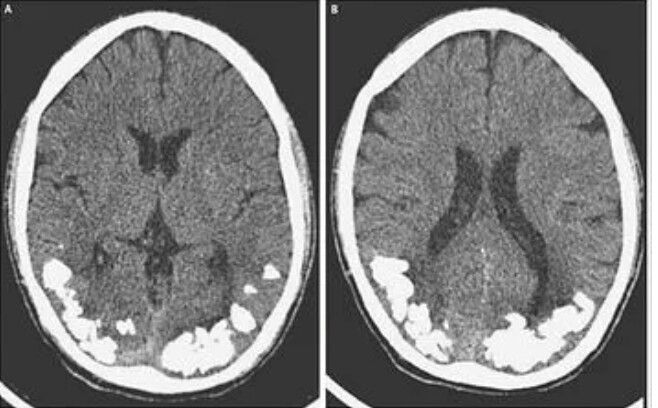

For 10 years a young man in Brazil had been suffering from throbbing headaches and vision problems. On close examination, it turned out there were small stone-like calcium deposits in his brain. This was apparently an extreme complication brought about by Celiac disease, an autoimmune disorder that over time affected the lining of the small reduced the body's ability to absorb nutrients. It is unclear how exactly celiac disease resulted in calcification in the brain, but researchers said it is possible that the patient's lowered ability to absorb iron may have had a role.